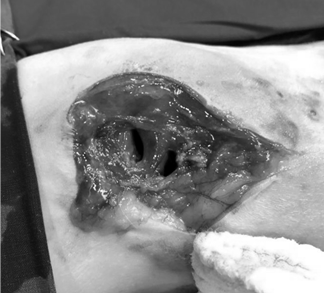

교상 사고로 인한 외상의 경우

겉보기에는 구멍 정도 밖에 안보이는 미약한 피부 찢김인 경우에도 그 밑의 피하 조직은 매우 심각한 손상을 입은 상태일 수 있습니다.

치료 없이 방치한 경우 폐혈증으로도 진행 될 수있으니 사고 후 바로 병원에 내원해야 합니다.

교상으로 인한

피부손상

근육손상

교상으로인한

복강천공